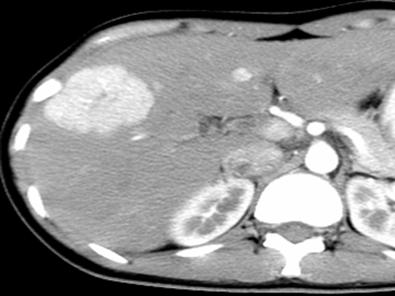

局灶性结节增生(FNH):年轻人多见,是由正常肝细胞、血管、胆管和kupffer细胞组成,无正常肝小叶结构,病灶中央为星状纤维瘢痕,向周围放射分隔,无包膜,与正常肝实质分界清楚,容易误诊,特别是需要和肝脏肿瘤相鉴别;

图中白色病灶为FNH